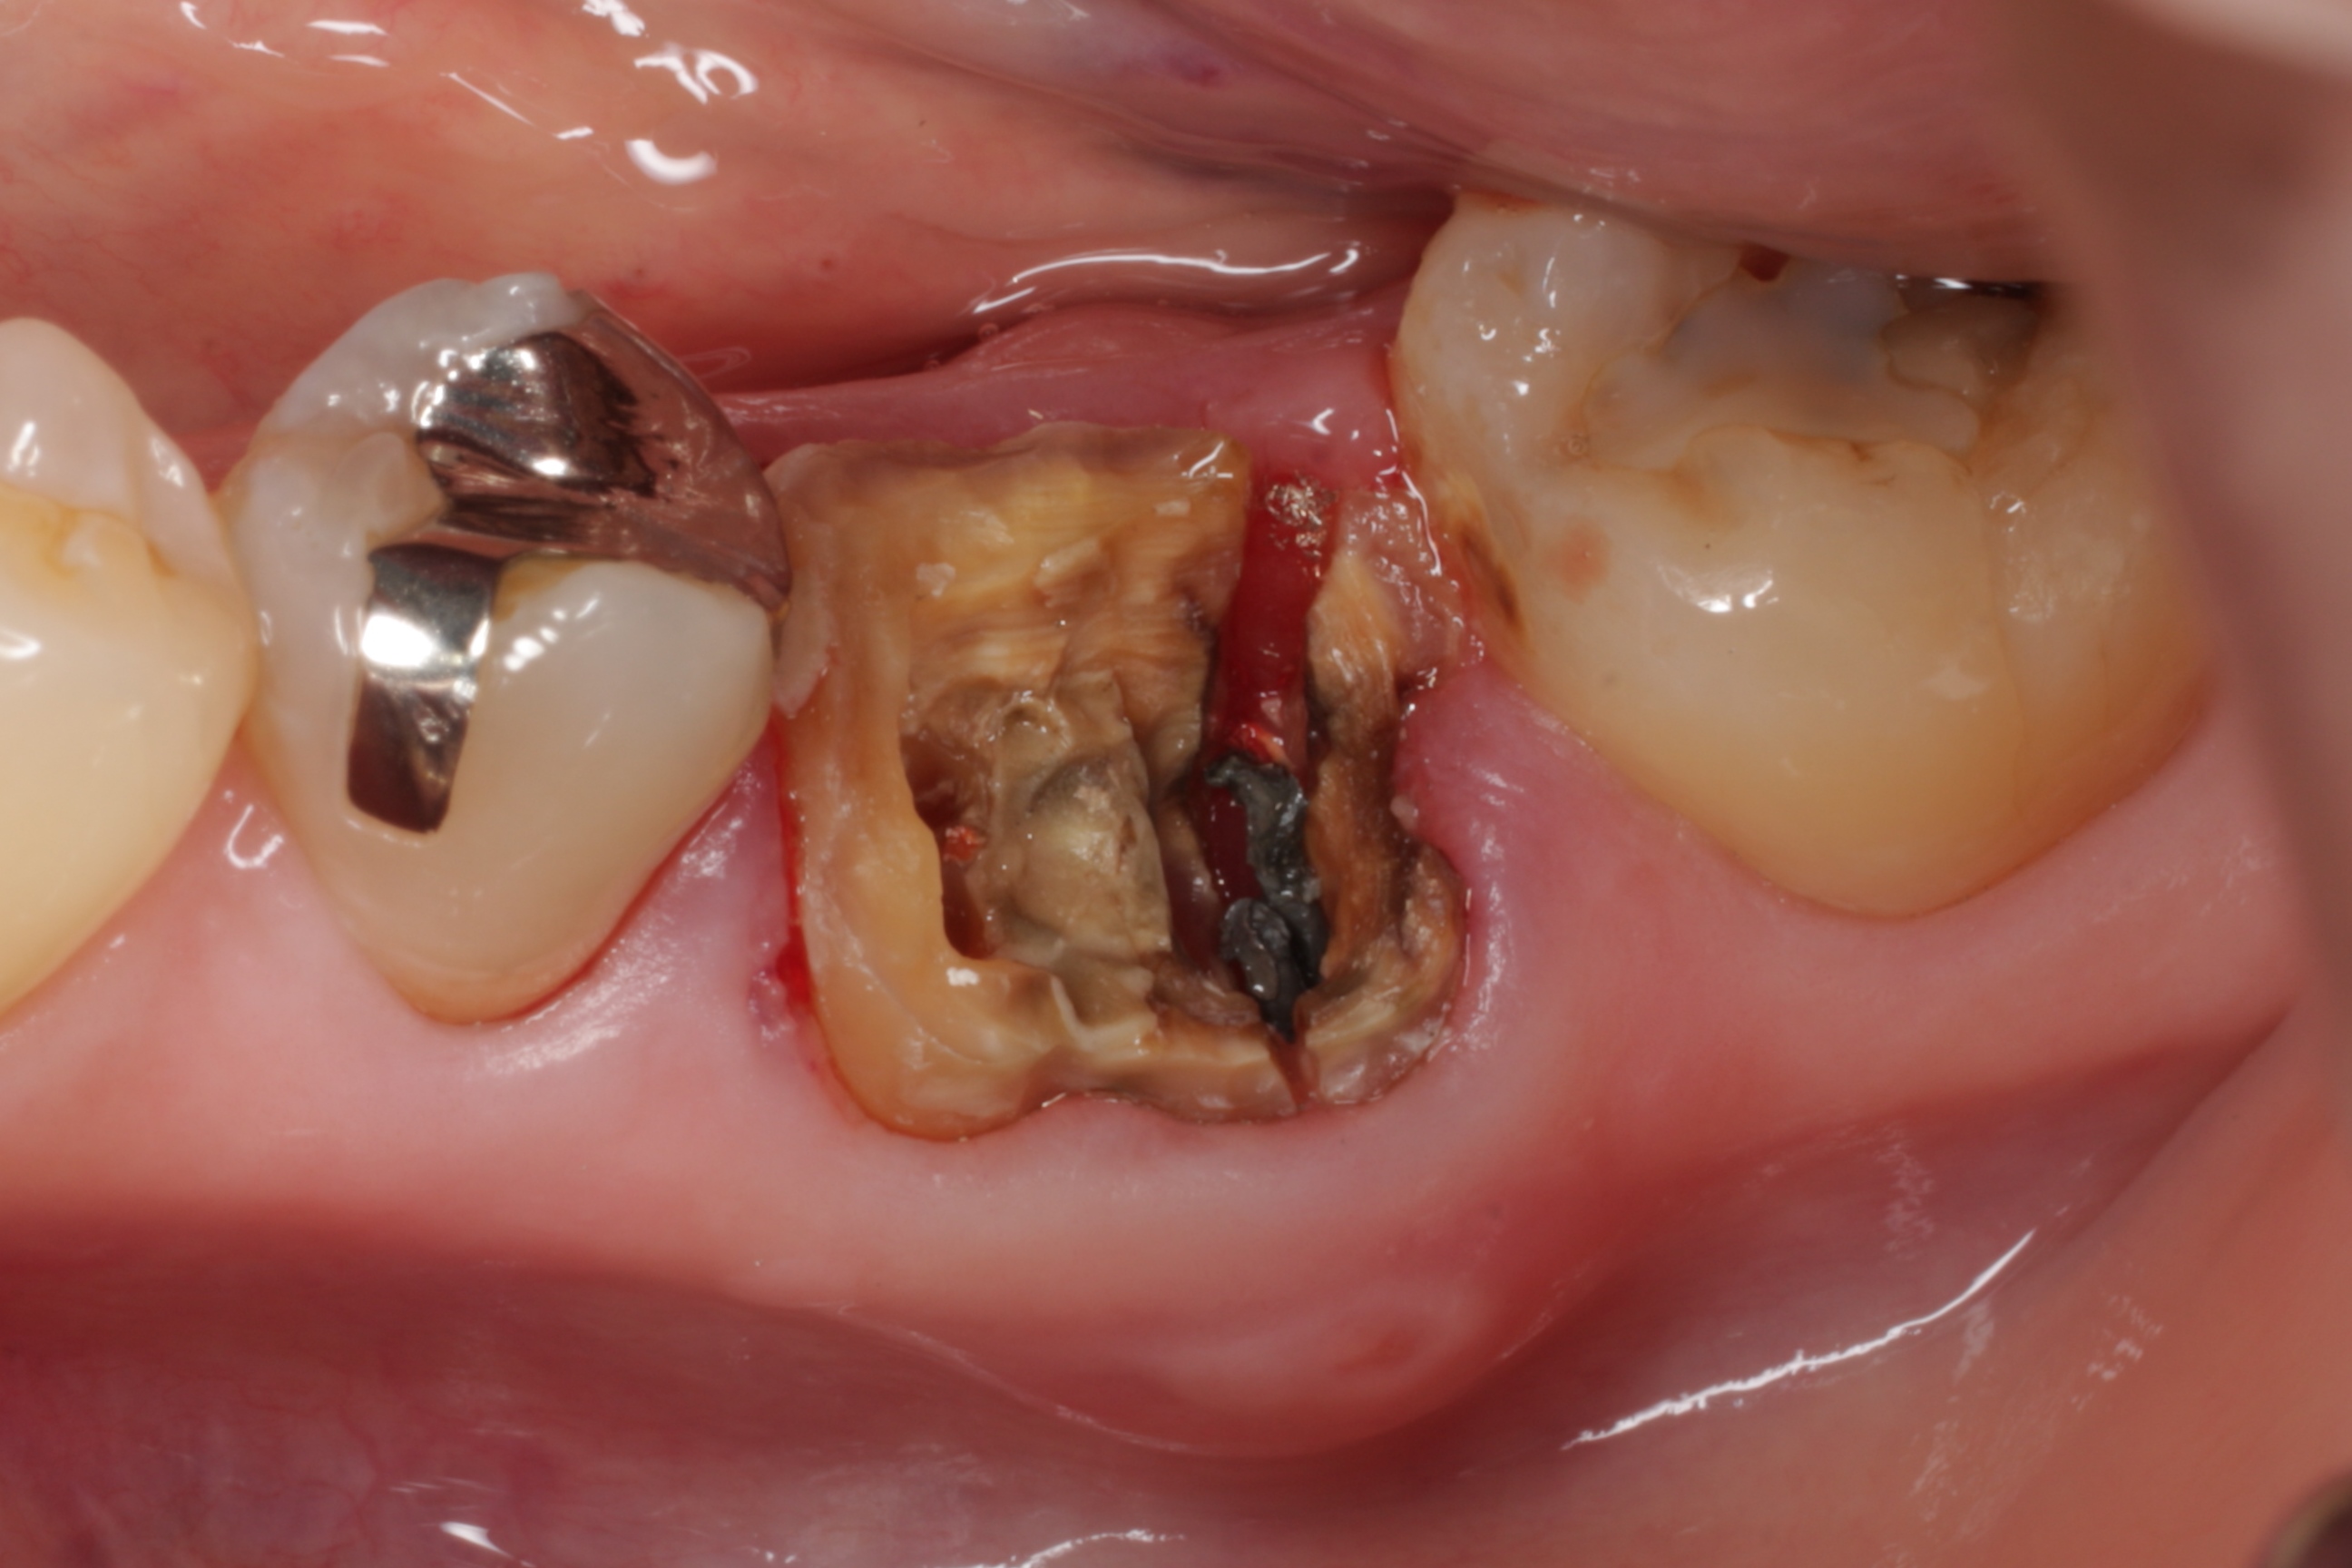

3年前に割れてしまった歯を抜いて、すぐに親知らずを移植しました。

3年経過した今では「全く違和感も無く、快適に使えています。」とおっしゃって下さいました。

インプラントにしていたら何十万円もかかった上に、所詮自分の歯ではありません。親知らずでも、虫歯や歯周病にさえしていなければ、立派に役に立ってくれる事があります。この親知らずがもしもボロボロの虫歯になっていたら、インプラントしか方法がなかったかも知れません。